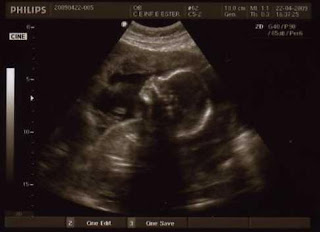

A semana passada fomos à eco morfológica, felizmente está tudo perfeito, a pipoca passou a eco a mexer os braços para cima e para baixo (são os genes de desportista dos pais) e a abrir e a fechar a boca (pensava que estava no Dragão e concerteza estava a cantar o hino!), de vez em quando olhava para nós e nós, claro, derretiamo-nos!

Saí da eco, por um lado feliz, porque as medidas estão todas consoante o tempo de gestação, mas por outro pensava que nesta eco se visse mais coisas, não foi muito diferente da eco que tinha feito na semana anterior, mas bom, o que importa é que a pipoca está linda.